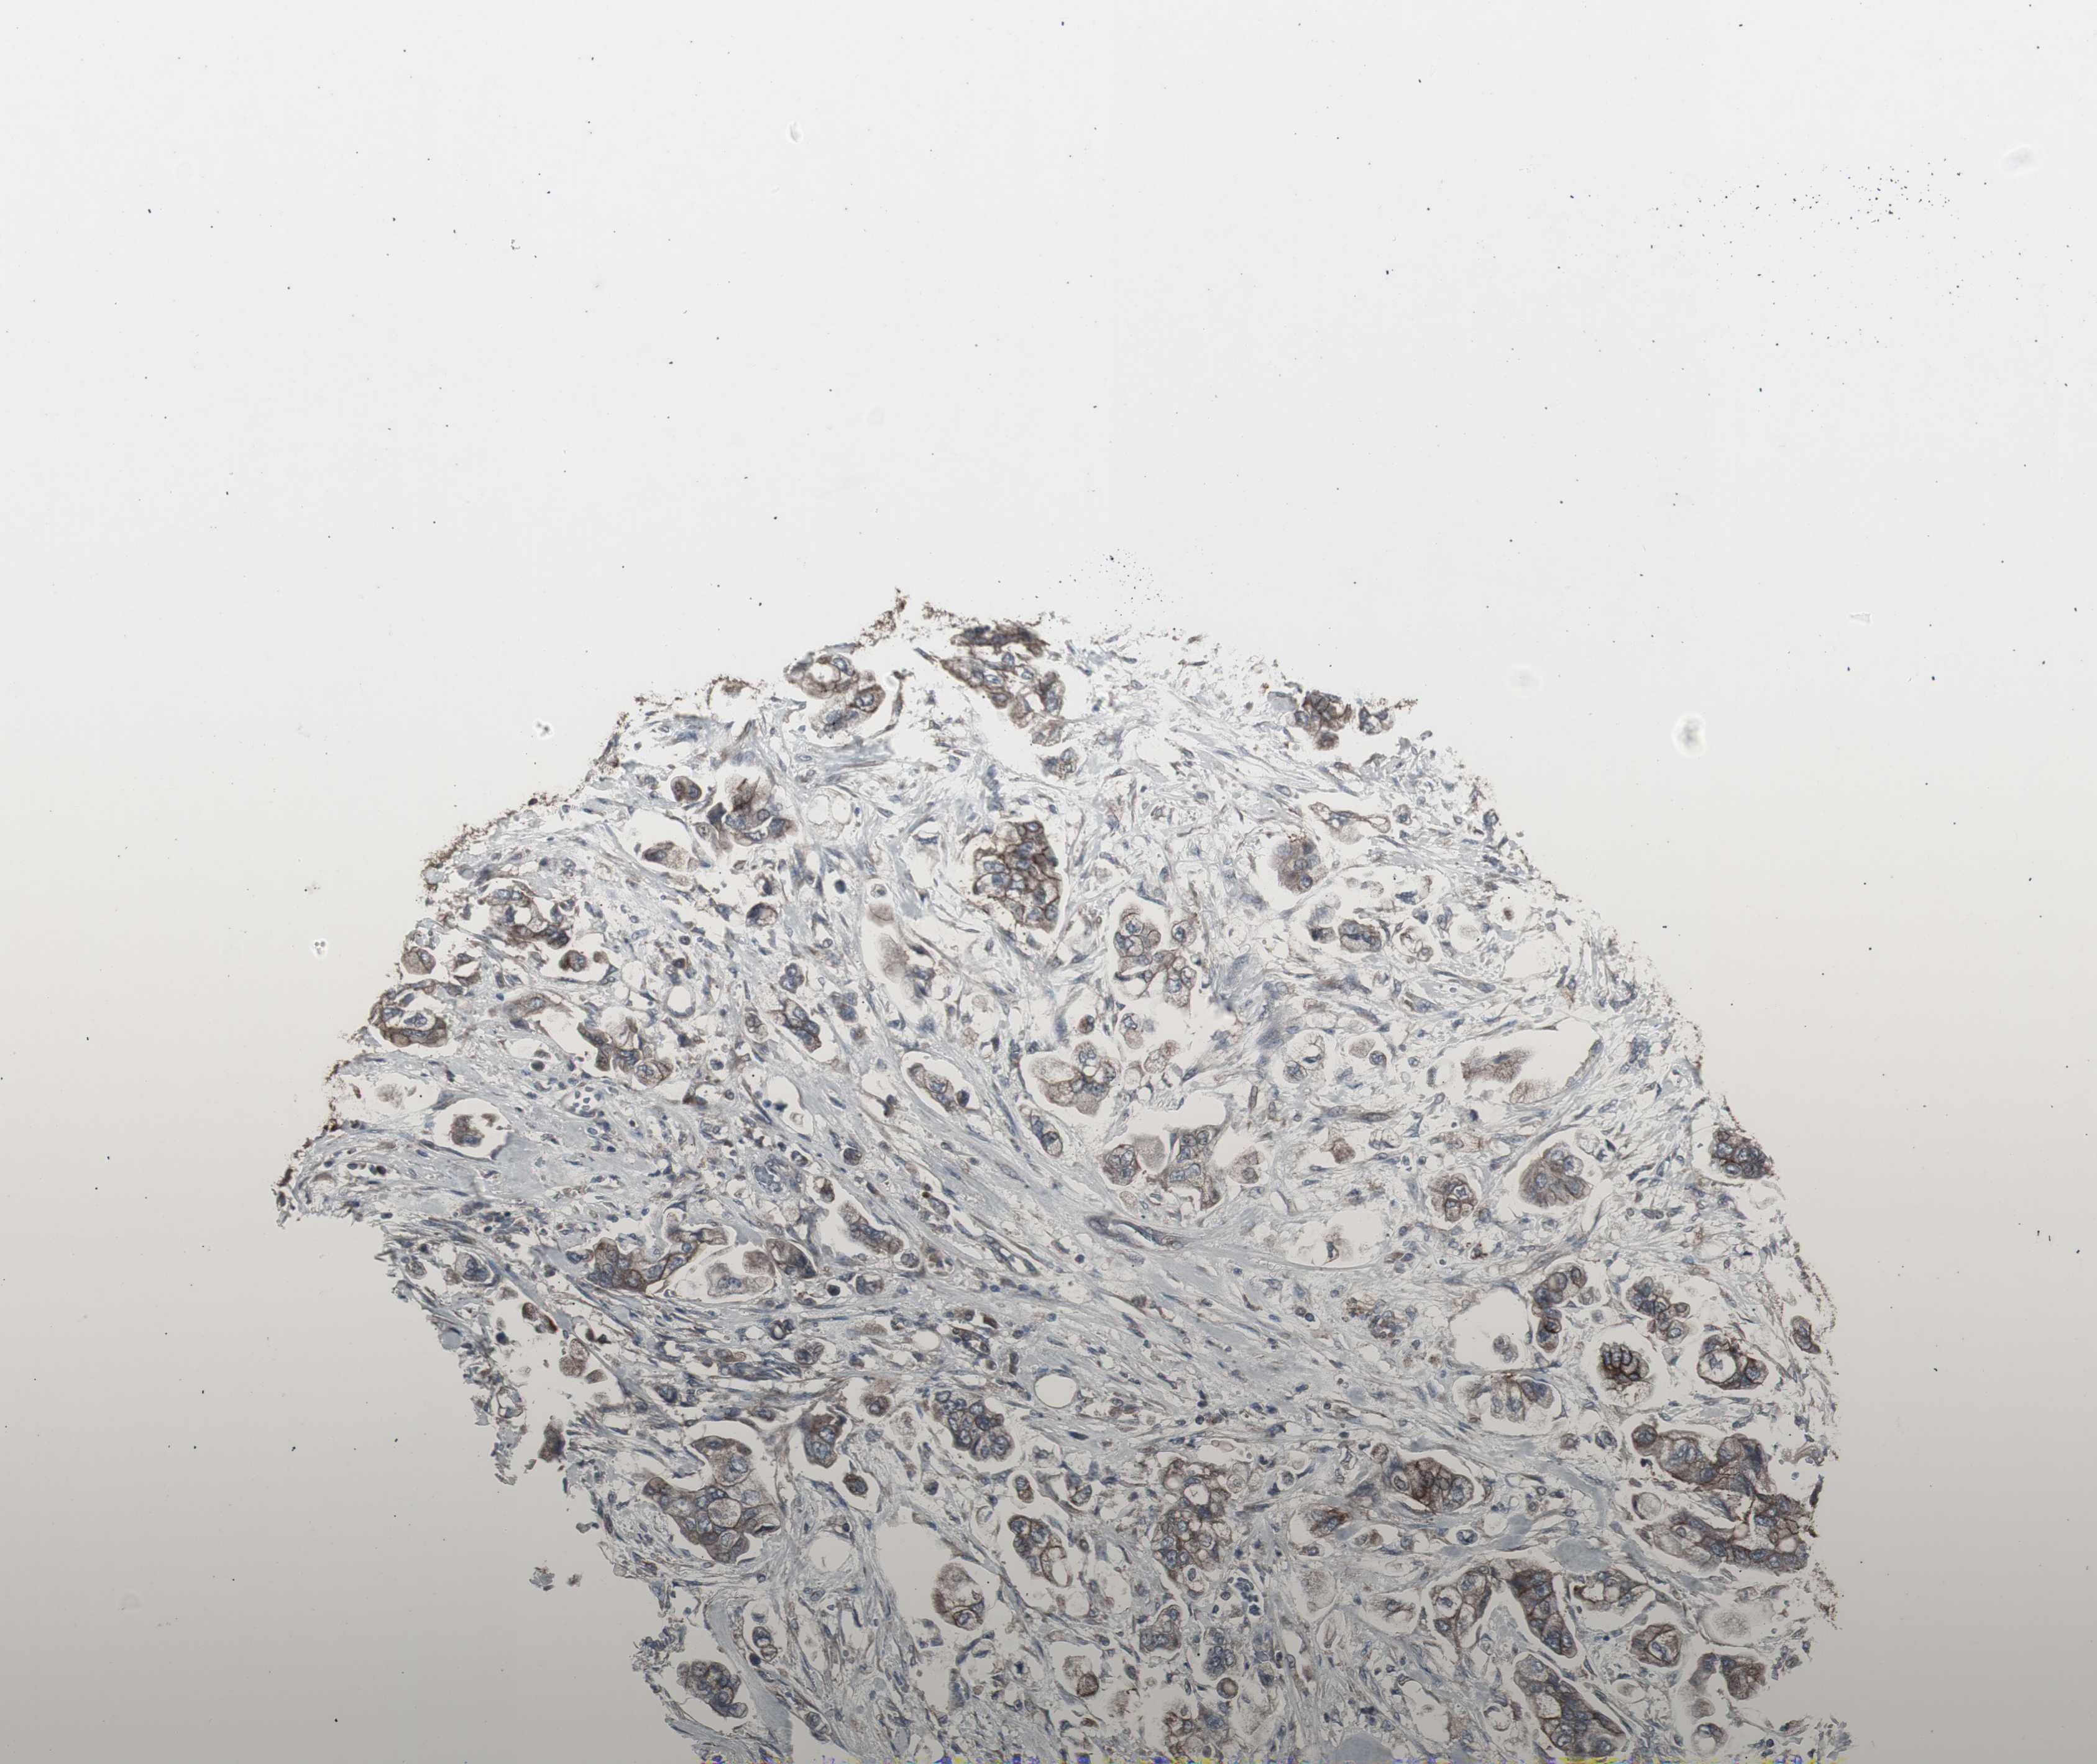

STOMACH CANCER - Protein expressioni

A mouse-over function shows sample information and annotation data. Click on an image to view it in a full screen mode. Samples can be filtered based on level of antibody staining by selecting one or several of the following categories: high, medium, low and not detected. The assay and annotation is described here.

Antibody staining in the annotated cell types in the current human tissue is reported as not detected, low, medium, or high, based on conventional immunohistochemistry profiling in selected tissues. This score is based on the combination of the staining intensity and fraction of stained cells.

Each image is clickable and will lead to virtual microscopy that enables deeper exploration of all samples and also displays staining intensity scores, fraction scores and subcellular localization as well as patient and tissue information for each sample.

Antibody HPA007264

Staining

High

Medium

Low

Not detected

Intensity

Strong

Moderate

Weak

Negative

Quantity

>75%

75%-25%

<25%

None

Location

Nuclear

Cytoplasmic/membranous

Cytoplasmic/membranous,nuclear

Adenocarcinoma, NOS

Adenocarcinoma, High grade